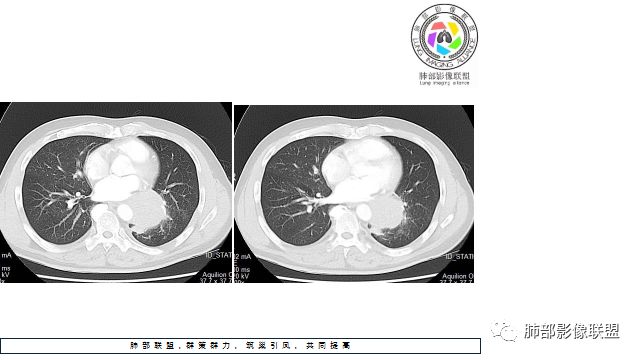

1.左下肺门区巨大肿块,支气管显示不清,轻度阻塞性炎症,没有明显肺不张,提示管腔受压狭窄可能性大于堵塞,这较少见于鳞癌。

2.病灶边缘光滑,未见明显分叶、毛刺,未见明显强化,这符合腺癌影像学特点,却符合神经内分泌癌表现。

3.病灶内密度均匀,轻到中度均匀强化,大病灶未见明显液化坏死区及空洞,不符合鳞癌而符合小细胞肺癌特点。

4.病灶内有肺动脉走形,血管局部受压,未见破坏,病灶乏血供,呈血管包埋或血管造影征;侵袭性力强及破坏力弱、血管漂浮都符合SCLC,所以鳞癌的可能性也不大。

5.左肺门块影或淋巴结肿大,竭力挤兑肺门血管结构,呈冰冻肺门;有时候SCLC可以单独呈现冰冻肺门,而没有没有冰冻纵隔。